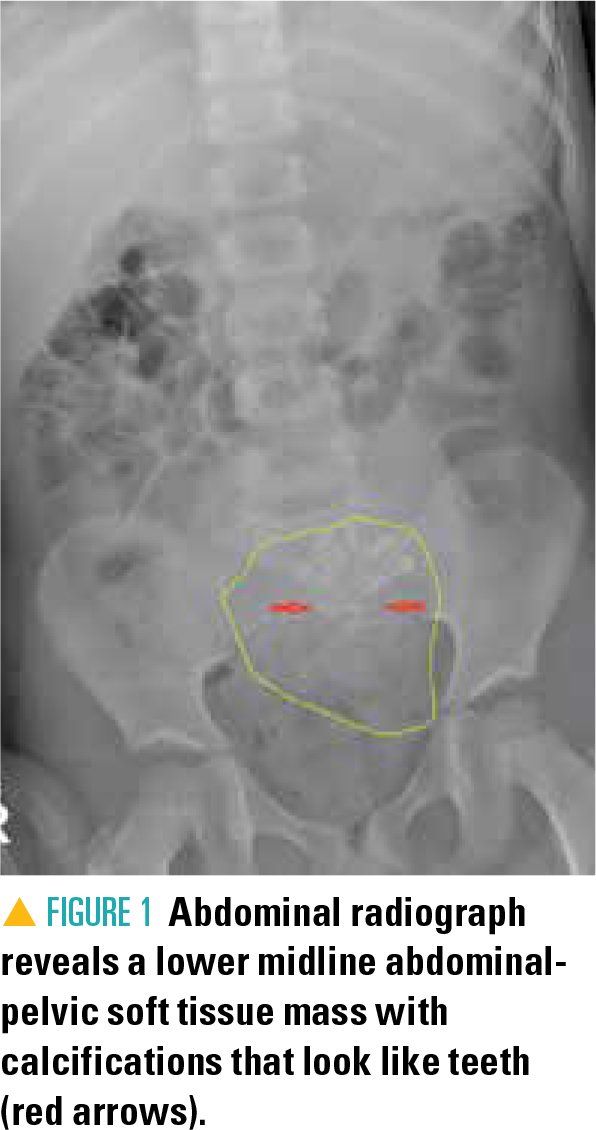

A complete blood count, basic metabolic panel, and clean catch urinalysis all were within normal limits, and fecal occult blood was negative. Abdominal radiograph revealed a lower midline, abdominal-pelvic soft tissue mass, with internal calcifications that looked like teeth (Figure 1). Bowel gas was present throughout, without obvious obstruction. Computed tomography (CT) of the abdomen and pelvis with contrast subsequently revealed a 7.0 x 6.2 x 5.4-cm unilocular, complex cystic mass within the left adnexa with internal calcifications (Figure 2).

Dermoid cysts have a characteristic appearance on ultrasonography and CT (a unilocular cystic mass containing fat, with or without calcification), allowing for reasonably accurate noninvasive diagnosis.4 Interestingly, the abdominal kidney/ureter/bladder (KUB) X-ray in this case was also strongly suggestive of the diagnosis, given the presence of calcifications that looked like teeth. Had the KUB not shown teeth, other common causes of acute abdominal pain, as well as intestinal obstruction, would have remained higher on the differential.